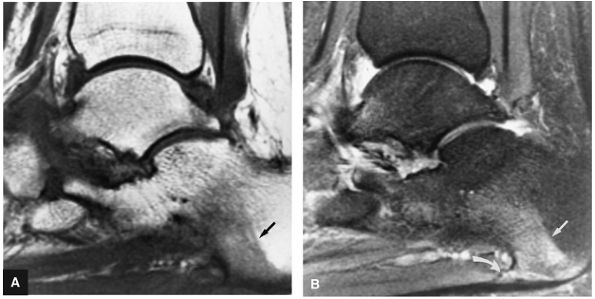

Stage I: Subchondral trabecular compression. Radiograph results are negative, bone scans are posi-tive, and marrow edema is seen on MR imaging (Fig. 5.95).

Stage III: Fluid around a nondetached, nondisplaced fragment (Figs. 5.98 and 5.99)

FIGURE 5.95 ● Stage I OLT with subchondral bone marrow edema, which is hypointense on the coronal T1-weighted FSE image (A) and hyperintense on the coronal FS PD FSE image (B). The overlying talar articular cartilage is hyperintense on the FS PD FSE image (B).